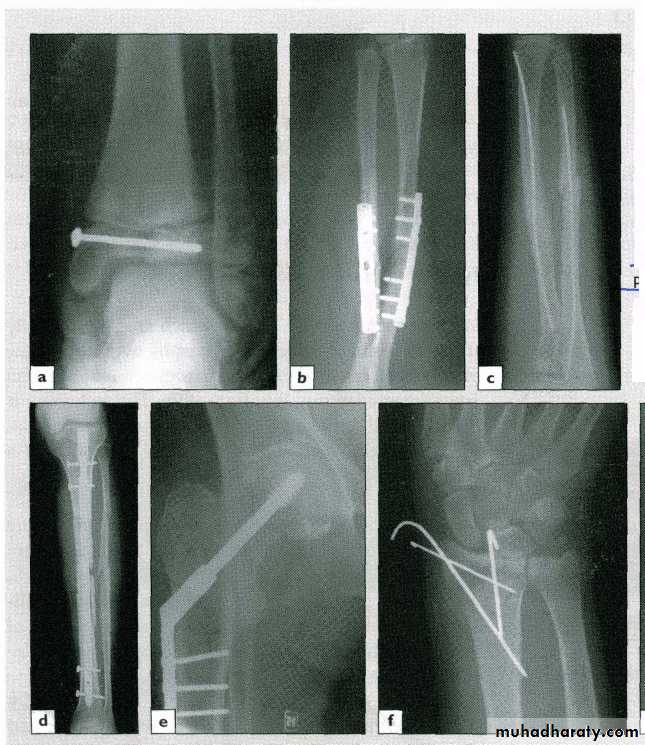

Internal fixation

Wires (e.g. Kirschner wire)

Screws

Plates

Intra-medullary nails

34Indications

OR. Needed

Unstable #

# of poor & slow healing e.g. FN.Pathological #

Multiple #sPatient with nursing difficulty

Adv. :

secure fixation

early joint motion

Disadv. :

soft t. damagerisk of infection

metal failure

37External fixation

Screws (Schanz) pass above & below the # and are connected to an external frame

39Indications

Open #

Closed # with severe s.t. damage

Infected ## with bone loss (bone lengthening)

Pelvic fracturesAnaesthetic risk